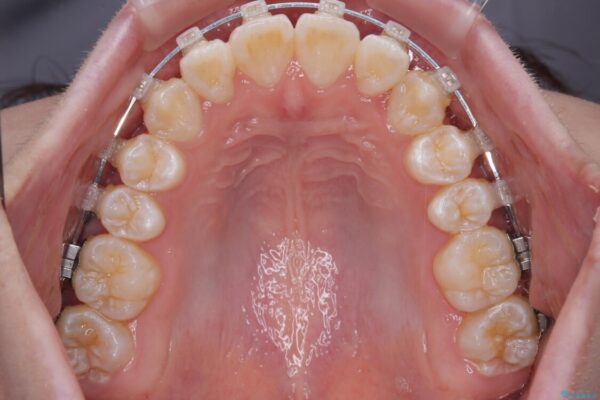

治療途中

• 【モニター】前歯のデコボコをスッキリ解消!目立ちにくいワイヤー矯正でスピーディに治療完了 治療途中画像

患者様の協力もあり、およそ1年間で治療を完了。スムーズな歯の移動を実現しました。

上下の正中(真ん中のライン)もずれることなく、バランスの取れた美しい歯並びに。笑顔に自信を持てる仕上がりとなりました。